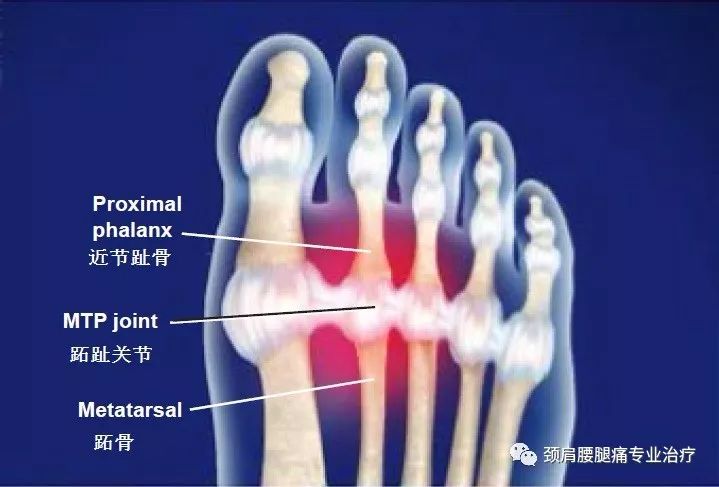

6518 趾关节屈曲包括槌状趾和锤状趾。槌状趾 (Hammertoe) 是指在脚趾中间的关节发生弯曲。锤状趾 (Mallet toe)是类似的一种足部疾病,但影响的是脚趾前端的关节。除此之外,两者在其他方面的差9015 跖趾关节metatarsophalangeal joint 由各跖骨小头与各趾的近节趾骨的中间底构成。 关节囊松弛,上面较薄,下面较厚,在跖侧及两侧有韧带加强。 跖趾关节属椭圆关节,可作屈伸及轻微的收展The protocol described in this paper showed that ultrasound is a reliable method to measure morphology of the toe flexor muscles The portability and advantages of ultrasound make it a useful tool for clinical and research settings

一、概述:跖趾关节疼痛是累及跖趾关节的疼痛,是一种常见的症状,几乎全部是由于关节面异常引起半脱位和关节囊与滑膜的撞击,最终导致关节软骨的破坏 (退行性关节病)。 详细 是否医保: 否 发病部位: 足部 关节 挂号科室: 骨科 内科 传染性:无传染性 治疗方法: 药物治疗、康复治疗、中医治 治愈率:85% 治疗周期:1030天趾关节下瘤 关节下瘤小而明显 内、外蹠突 外蹠突小,内蹠突长椭圆形,约为内趾长之半,有内跗褶 皮肤、体色 背部皮肤粗糙,体背面有数行长短不一的纵肤褶,褶间、体侧及后肢背面有小疣粒;体腹面 (一)望诊 1.踝关节肿胀 常见的原因是踝部筋伤、骨折、踝关节结核、骨性关节炎等造成肿胀。 2.足踝部畸形" (1)马蹄足:行走时前足着地负重,踝关节跖屈位,足跟悬起。 (2)仰趾足:行走时足跟着地负重,

第一跖趾关节 搜狗百科

跖趾关节痛 搜狗百科

什么是第一跖趾关节 有来医生